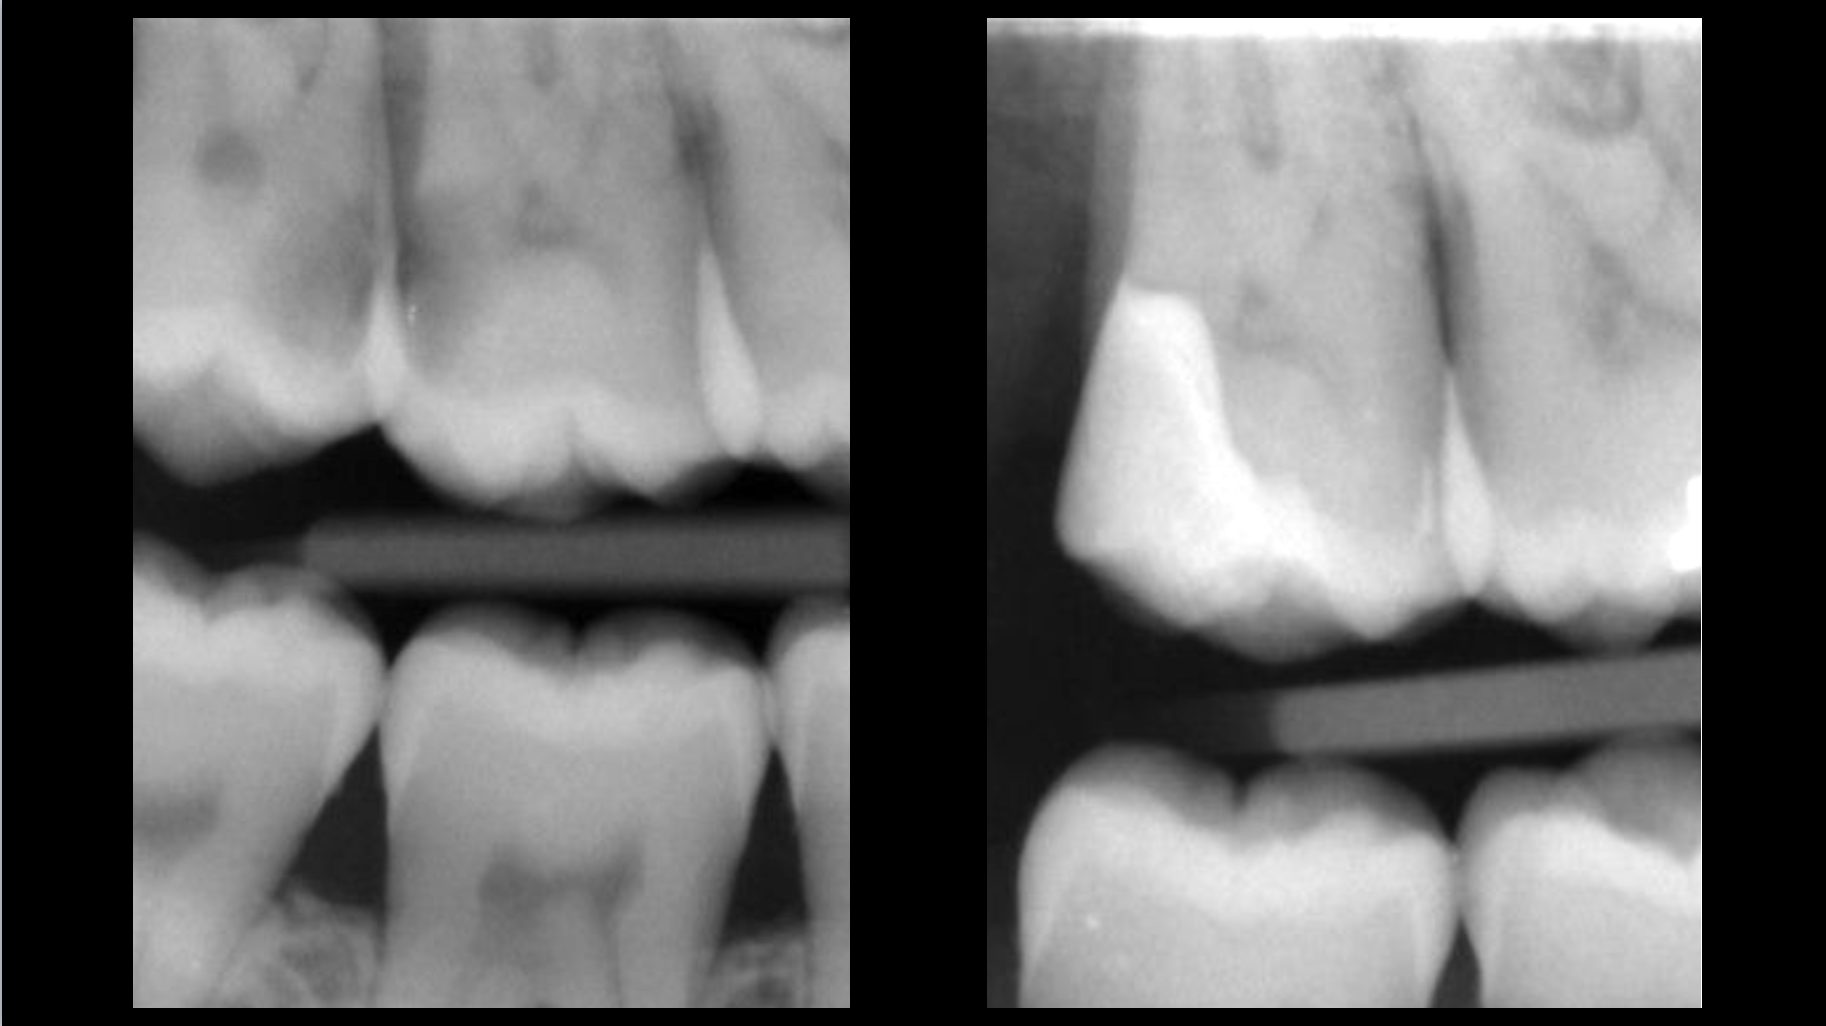

Cas clinique

Traitement canalaire : 80-95% de taux de succès

Cas clinique

Retraitement canalaire : 80-95% de taux de succès